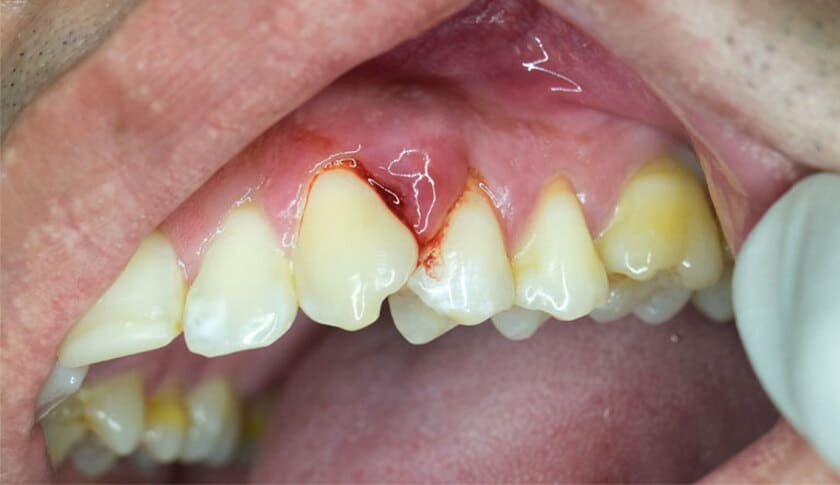

Chảy máu chân răng thực chất là chảy máu từ lợi và nướu

Viêm nướu

Viêm nướu là tình trạng nướu bị sưng tấy, viêm nhiễm, nứt vỡ dẫn đến chảy máu. Bệnh lý này có thể do thói quen vệ sinh răng miệng không tốt, không loại bỏ hết thức ăn thừa và cao răng bám ở chân răng. Lớp vôi tích tụ càng nhiều và không được loại bỏ định kỳ sẽ gây ra viêm nướu và dẫn đến chảy máu. Người bệnh nên đến gặp bác sĩ để lấy vôi răng định kì, làm sạch vùng kẽ răng và điều trị viêm nướu thì tình trạng chảy máu mới có thể được cải thiện.